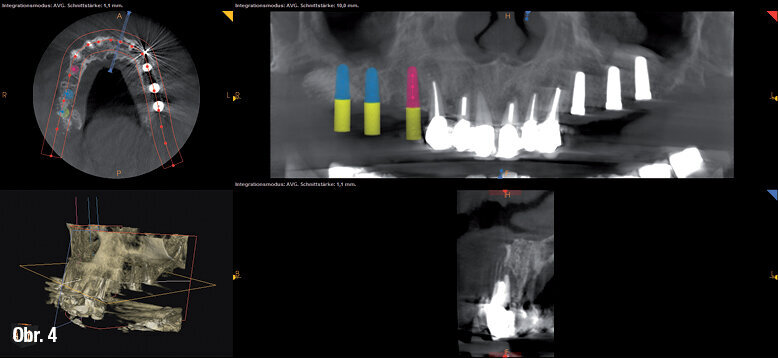

Po naplánování pomocí simulace na dentálním CT (příklad na obr. 4) a po odublování imediátní protézy jako operační šablony byly ve třetí a poslední fázi zavedeny implantáty do horní čelisti (obr. 5).

Ukázka plánování implantátů pomocí dentálního CT